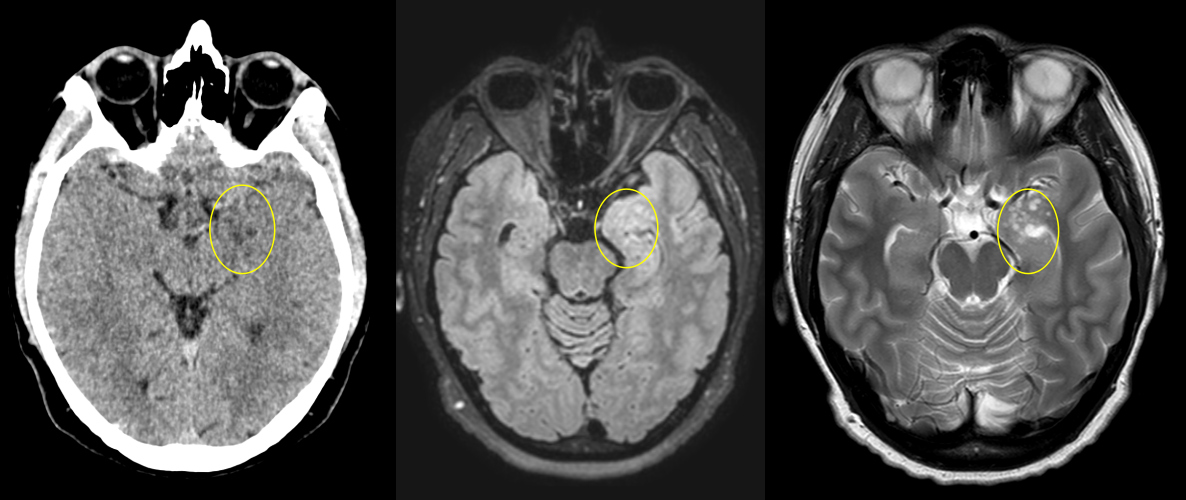

– CT cerebral – util doar ca evaluare inițială; are sensibilitate scăzută și poate trece frecvent cu vederea o tumora de dimensiuni reduse.

Gliom de grad mic de hipocamp stâng – comparație CT – RMN